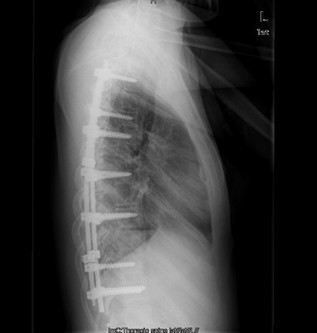

初步诊断:特发性脊柱侧凸(Lenke:ⅡA ̄型) 诊疗计划: 拟经后路脊柱侧凸矫形+同种异体骨植骨+椎弓根螺钉内固定术术

术中见胸椎脊柱S形侧弯,肌肉韧性较差,棘突偏离中线,凹侧小关节退变明显,胸段脊柱以T8为中心明显右凸,T4为中心向左侧凸起,右侧剃刀背畸形。